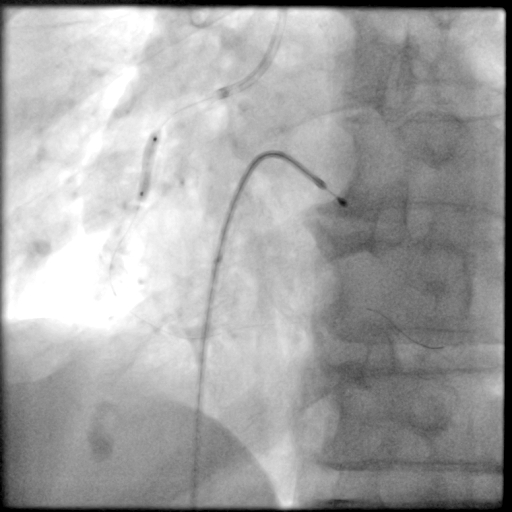

冠脉造影

PCI过程-球囊PTCA

预置临时起搏器后,7F AL1.0无法到位,更换为7F SAL1.0至RCA开口,应用非顺应性球囊2.5X15mm,于RCA中段病变处以12-18atm扩张,球囊膨胀不佳。